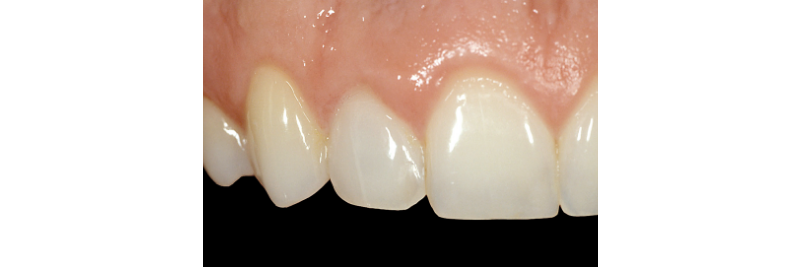

It must be stated that ample access preparation (Figs. 2A, 2B) is not required to internally bleach non-vital teeth, as a larger access preparation further compromises the tooth structurally. Figures 3A and 3B illustrate successful outcomes with a much more conservative approach (treatment by Dr. Steve Baerg, Gig Harbor, Washington).

So, the next time you come across a dark tooth in the esthetic zone, ask yourself if internal bleaching is a possible treatment solution before you pick up the handpiece.